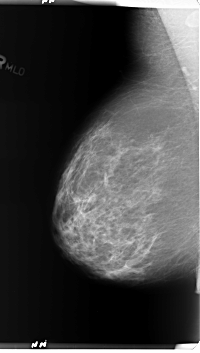

B_3367_1.RIGHT_MLO

RIGHT_MLO LINES 5992 PIXELS_PER_LINE 3392 BITS_PER_PIXEL 12 RESOLUTION 50 NON_OVERLAY